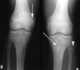

Osteopetrosis infantile form with nervous system involvement

Infantile osteopetrosis